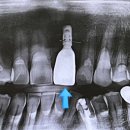

• 태종빌딩(고려병원 신관) | 앞니 임플란트] 윗앞니 임플란트 눈에 잘 띄는 위치여도 자연스럽게 완성해 드린 후기, 공덕 앞니 임플란트

저희 병원에 내원하셨던 ‘앞니 상실 후 자연스러운 임플란트 치료’를 받으신 환자분의 사례를 통해 치료 과정을 자세히 보여드리겠습니다. [치료 전, 후 미리 보기] 치료 전 ↓ 치료 후 앞니 임플란트, 자연스럽게 가능할까요? 치료 기간: 24/10/8~25/1/15 45세 남성분이 내원하셨어요. ​ 환자분의 윗 정중앙 앞니가...

안 아프고 편안한 치과, 마포 연세엘치과(2025-10-21 20:47:00)